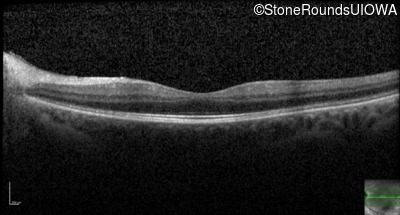

Optical Coherence Tomography - Left - 20/25 -1 sc

Exemplar / OCT Stack

OCT Stack